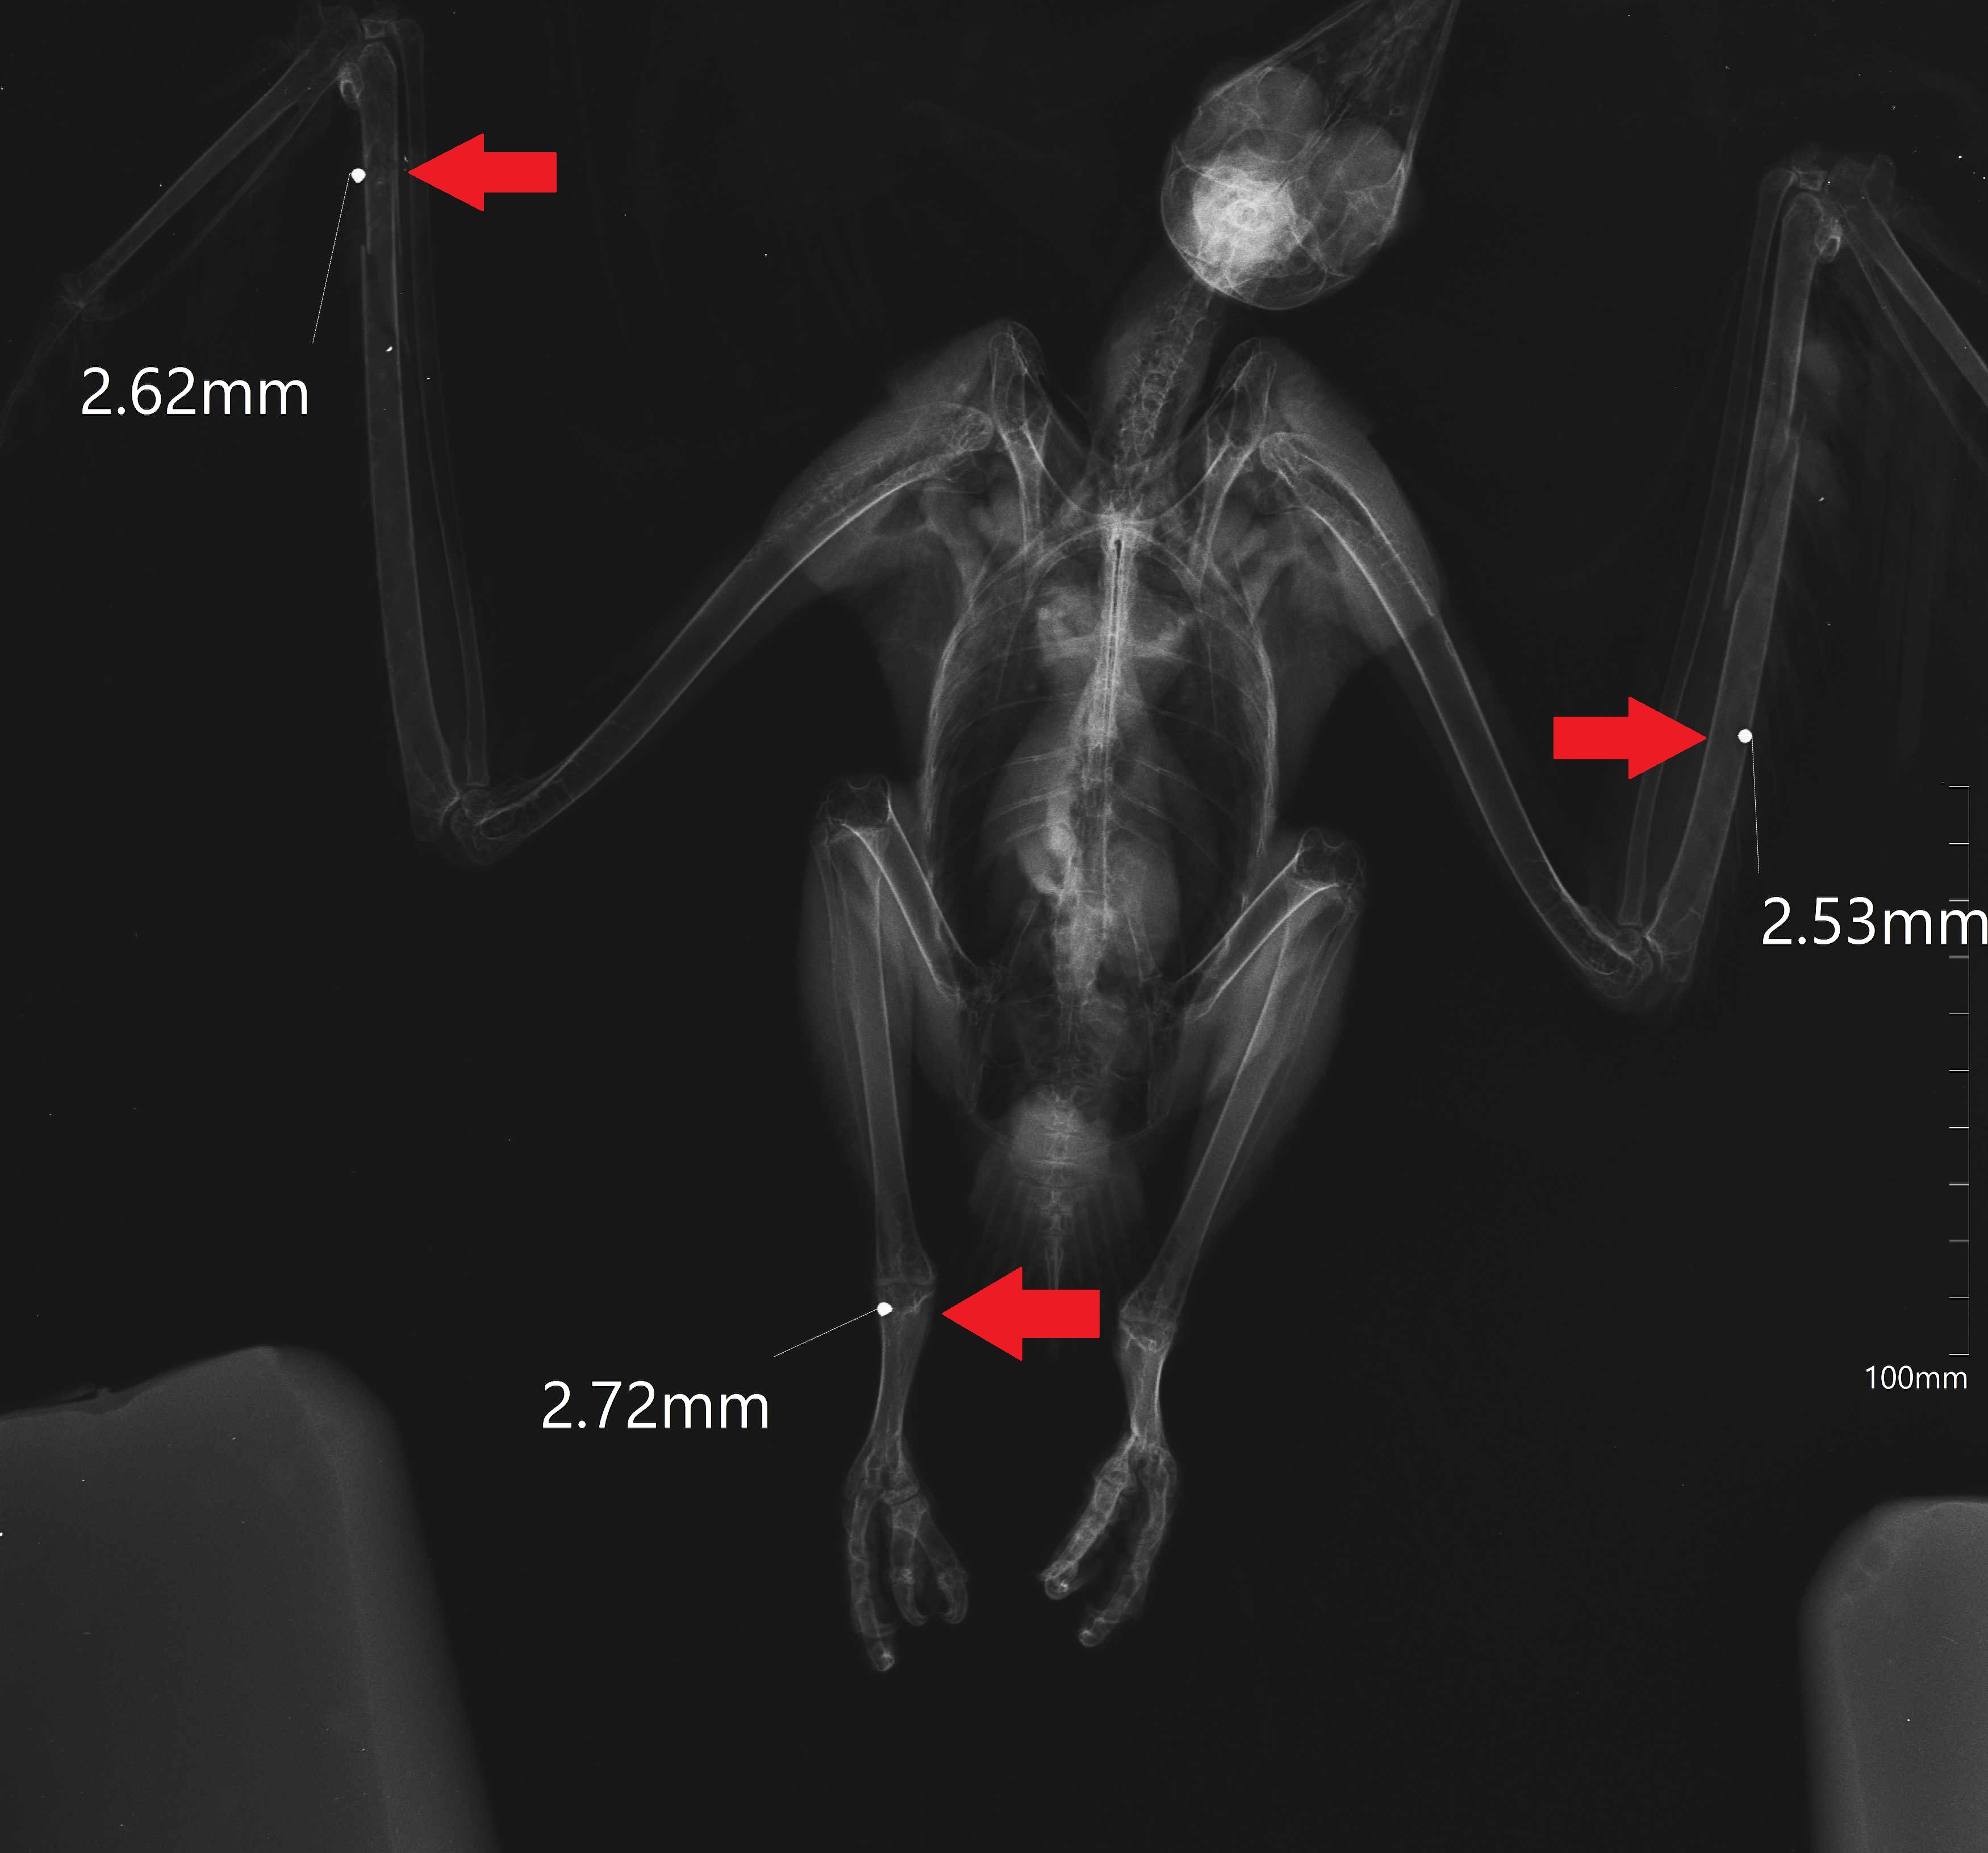

A terceira espécie, alvo da mesma crueldade, foi um milhafre-preto (Milvus migrans), uma ave de rapina que se alimenta principalmente de animais mortos, e que migra para Portugal em Março para nidificar.

Infelizmente, nem sempre é bem recebido por todos. Durante o exame físico, foram encontradas fraturas em ambos os cúbitos, correspondentes a dois dos três locais onde foi atingido por chumbo.

| Raio-x de duas gaivotas, onde é possível observar os chumbos. |